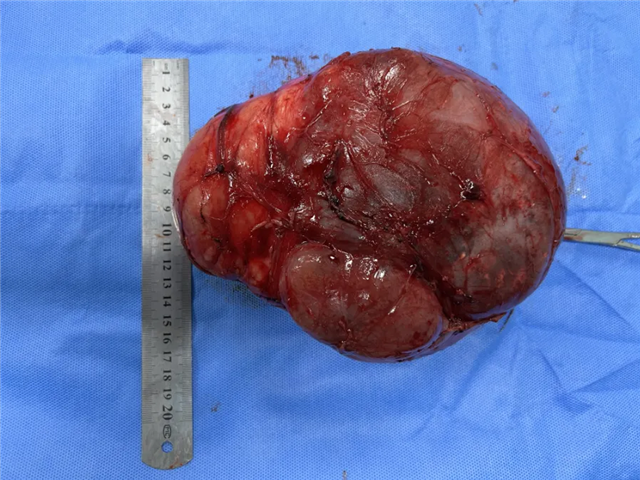

在北京儿童医院儿外科专家黄柳明主任和李现令教授的指导下,2024年07月31日,我院小儿外科团队在麻醉科的配合下将患儿肿瘤顺利切除。切下的肿瘤大小约19cm×16cm×11cm,内含脂肪、骨骼、囊液等。